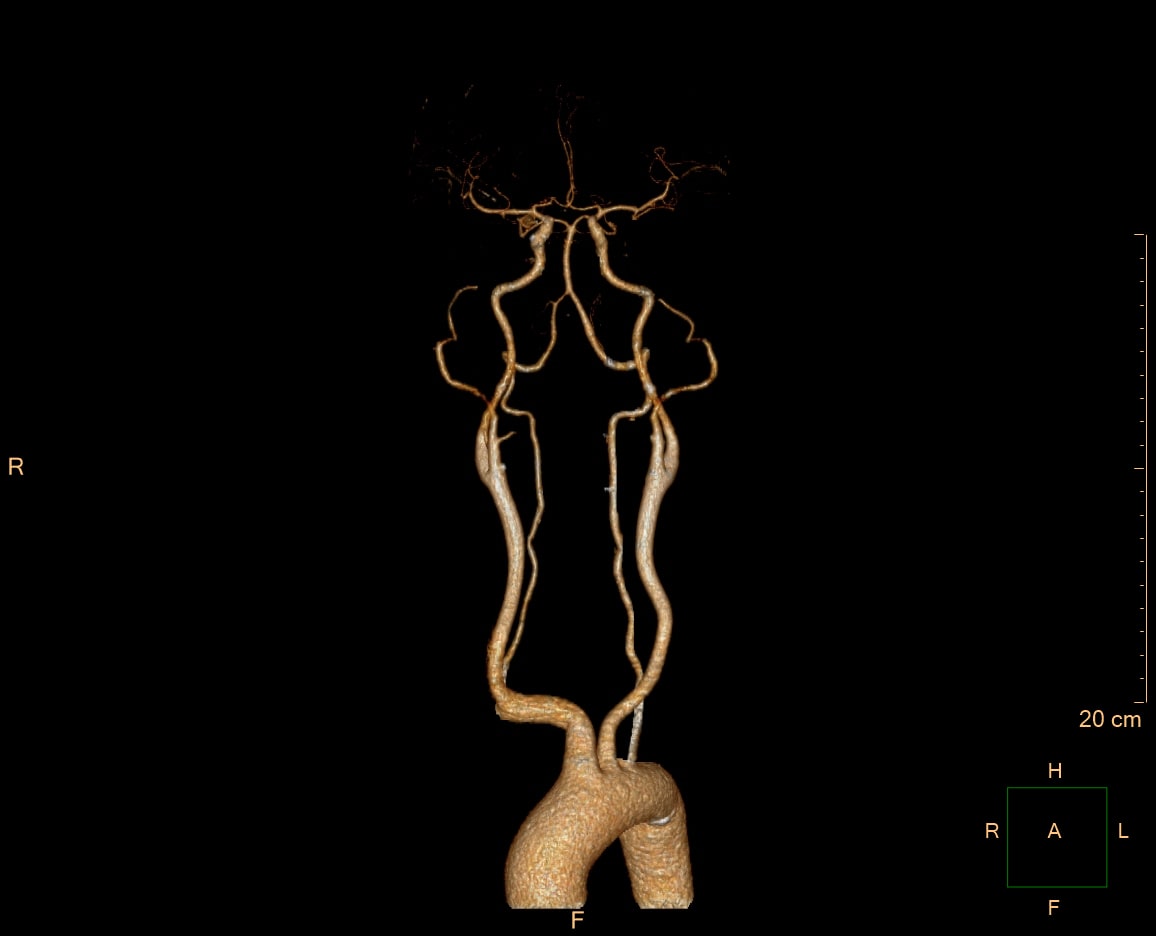

- 혈관 조영술: 혈관 내 혈전, 혈관의 좁아짐 등을 MRI 검사보다 정확하게 확인할 수 있습니다.